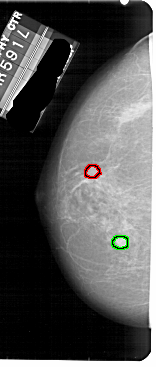

A_1853_1.LEFT_MLO

FILE: A_1853_1.LEFT_MLO.OVERLAY

TOTAL_ABNORMALITIES 1

ABNORMALITY 1

LESION_TYPE MASS SHAPE ROUND MARGINS CIRCUMSCRIBED

ASSESSMENT 2

SUBTLETY 4

PATHOLOGY BENIGN_WITHOUT_CALLBACK

TOTAL_OUTLINES 1

BOUNDARY

ABNORMALITY 2